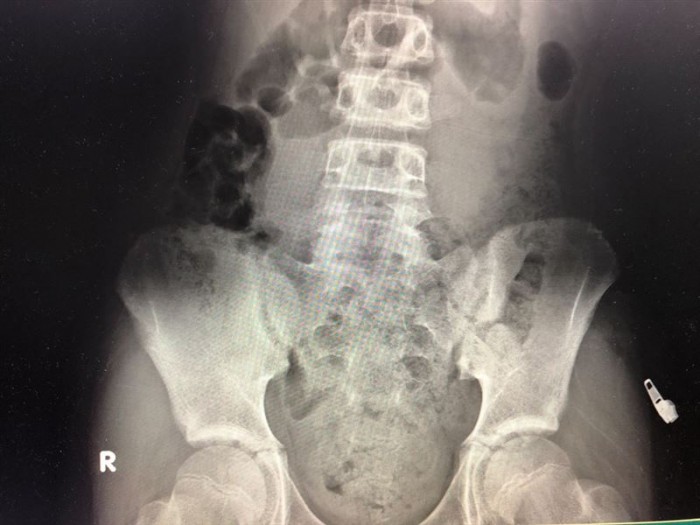

Sau khi chụp X-quang, bác sĩ phát hiện ruột của bé trai này chứa đầy phân. Cũng trong ngày hôm đó, bác sĩ Ngô tiếp nhận 3 trường hợp tương tự.